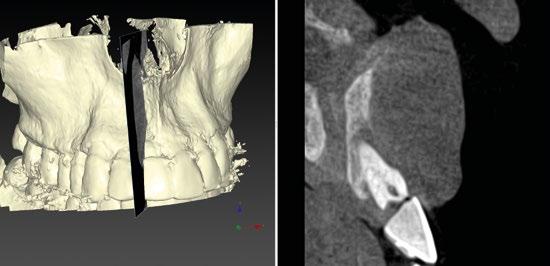

Por otro lado, es imprescindible y fundamental realizar un CBCT de la arcada a tratar para poder visualizar los tejidos duros y hacer una primera valoración del lecho implantario y de la patología existente. (Figura 4)

Otra prueba imprescindible hoy en día para nosotros es la realización de un escaneado intraoral que nos aporte la información de los tejidos superficiales y fusionado con el CBCT nos permita valorar los tejidos blandos del paciente. (Figura 5)

Para manejar todos estos datos vamos a necesitar de un software de diagnóstico y planificación digital como es el de DTX

StudioTM Implant en el cual vamos a abrir tanto el CBCT como el escaneado intraoral y nos va a permitir fusionar ambas mayas utilizando la herramienta SMARTFUSION. En un caso como éste, donde tenemos un incisivo central, superior, derecho, fracturado que vamos a extraer debemos realizar previamente la extracción Virtual

en el modelo digital para poder incorporarlo a la planificación de nuestro software. (Figuras 6 y 7)